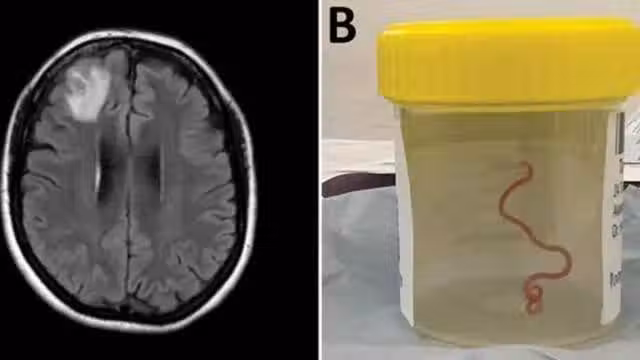

震驚!澳女子大腦取出8厘米蟒蛇體內蛔蟲,取出時還在蠕動_患者_手術_醫生